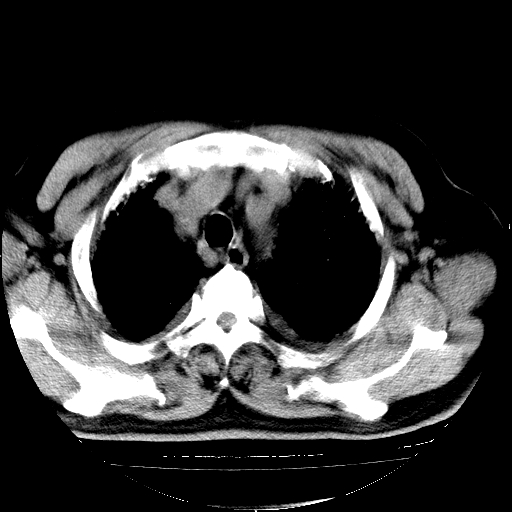

男,68岁,咳嗽、胸闷、发烧三天,查体:双肺散在湿罗音。

首先考虑特发型肺间质纤维化;两侧少量胸腔积液。

依据:1、两肺广泛条索状、网格状、蜂窝状改变。

1.双肺间质纤维化并感染;

2.双肺慢支炎肺气肿;

3.支扩并感染;

4.肺原性心脏病;

5.双侧胸腔少量积液;双侧胸膜增厚。

慢性支气管炎伴感染、肺气肿;间质性病变;双侧胸腔积液。

双肺多发条索状、网格状及小灶状密度增高影。考虑慢支合并感染.间质纤维化,双侧少量胸腔积液

两肺广泛条索状、网格状、蜂窝状改变。肺间质纤维化,肺心病,双侧胸腔积液